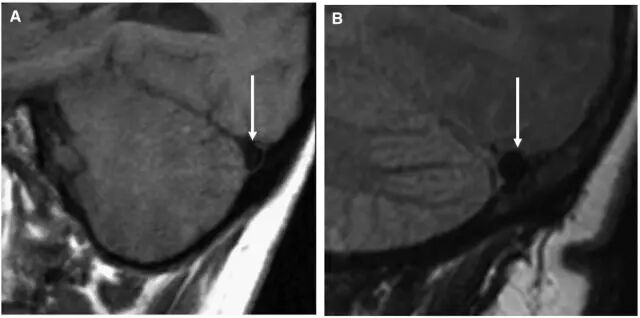

图11. A为正常的横窦,B为扩张的横窦。

图12. A为正常脑组织矢状位,B可见脑组织下坠。